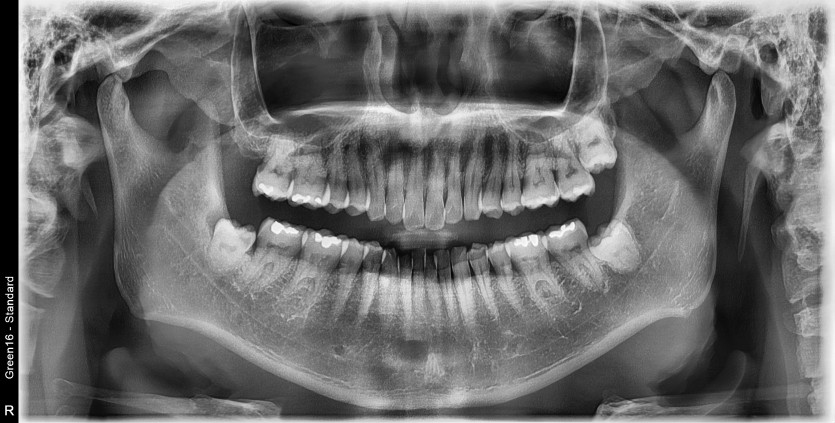

#28,38,48 사랑니 발치

구강 외과 전문의가 당일 발치했습니다.